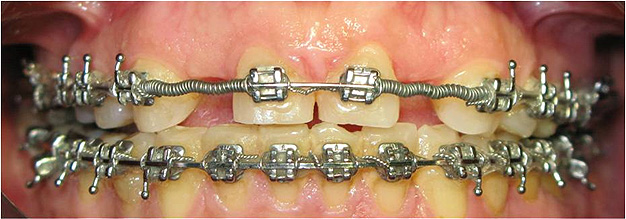

Caso 4 - Agenesia dos incisivos laterais superiores - tratamento ortodôntico para encerramento de diastema e implantes

![]() |